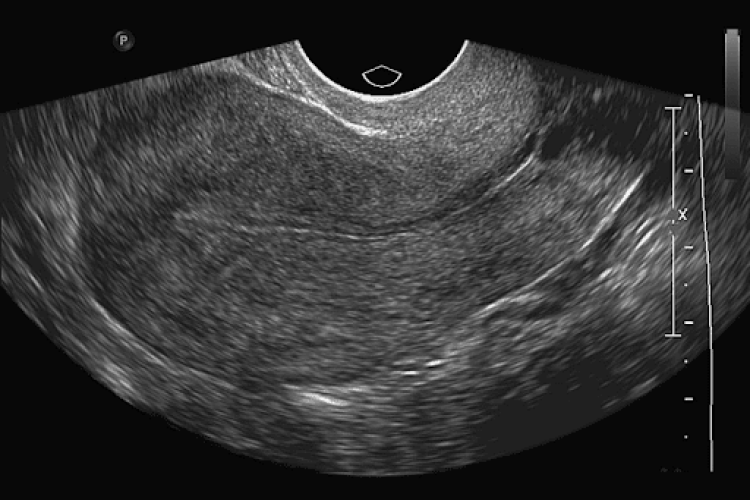

ECOGRAFIA TRANSVAGINAL

ECOGRAFIA TRANSVAGINAL COM DOPPLER

ECOGRAFIA TRANSVAGINAL PARA CONTROLE DE OVULAÇÃO

ECOGRAFIA TRANSVAGINAL OBSTÉTRICA (ATÉ 9 SEMANAS)